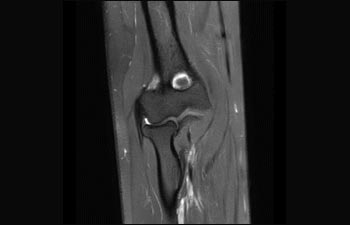

Plexus brachialis

Läsion am Plexus brachialis